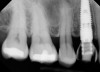

Management of the peri-implant papilla has generally been considered to be a challenge in the esthetic zone. It is worth noting though, that a shortened papilla is not an indication of a biologic problem, merely an esthetic one. The study of average papilla heights and volumes around natural, healthy teeth has been thoroughly explored with fairly clear and consistent outcomes.10 Between adjacent implants of similar design, the papilla height from the crest of bone has been less predictable, ranging from 1 mm to 7 mm with an average of 3.4 mm11 (Figure 2). Use of varying implant designs (platform-switched, conical connections, tissue-level, etc.) would likely increase the data divergence. Factors that are largely outside of the control of the treatment team but will bear heavily on the mature height of the papilla include: patient genetics, tissue biotype (thickness), oral microbiology makeup, and oral hygiene. Factors within the control of the treatment team include: implant diameter, volume of the peri-implant bone, position of the bone on adjacent natural roots, implant connection design, inter-implant distance, and the shape of the emergence profile.

Fig 2. The esthetic zone often presents with the challenge of two adjacent edentulous spaces. Use of two implants creates a stronger restorative solution, but at the expense of the inter-implant papilla. The average papilla height between adjacent implants is a mere 3.4 mm.